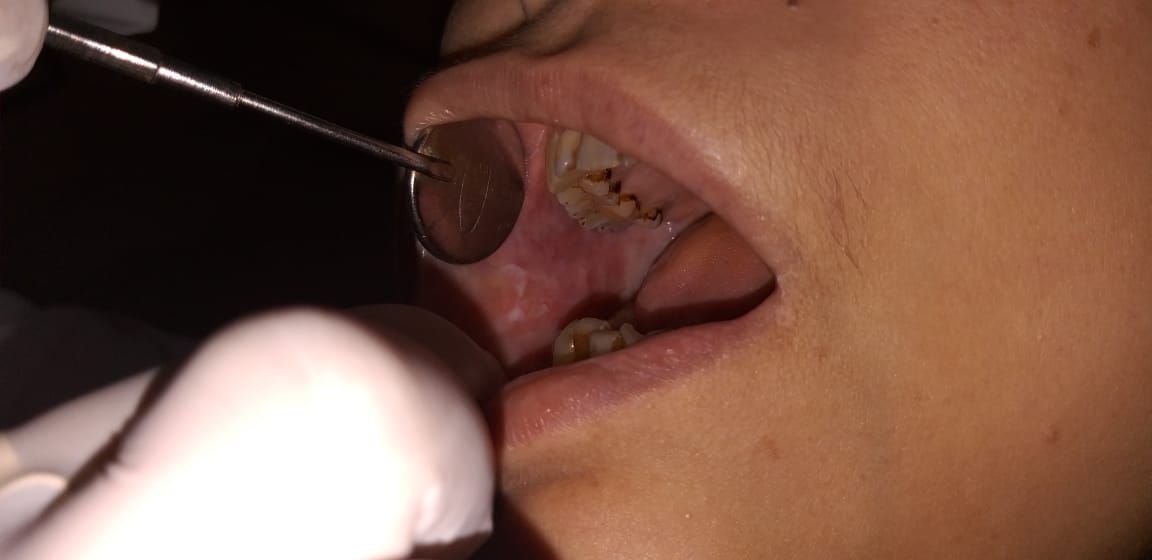

Chronic periodontitis, considered as the 6th complication of diabetes is detected early by dental check up. Other oral manifestations of diabetes can also be detected early and treated with utmost care.